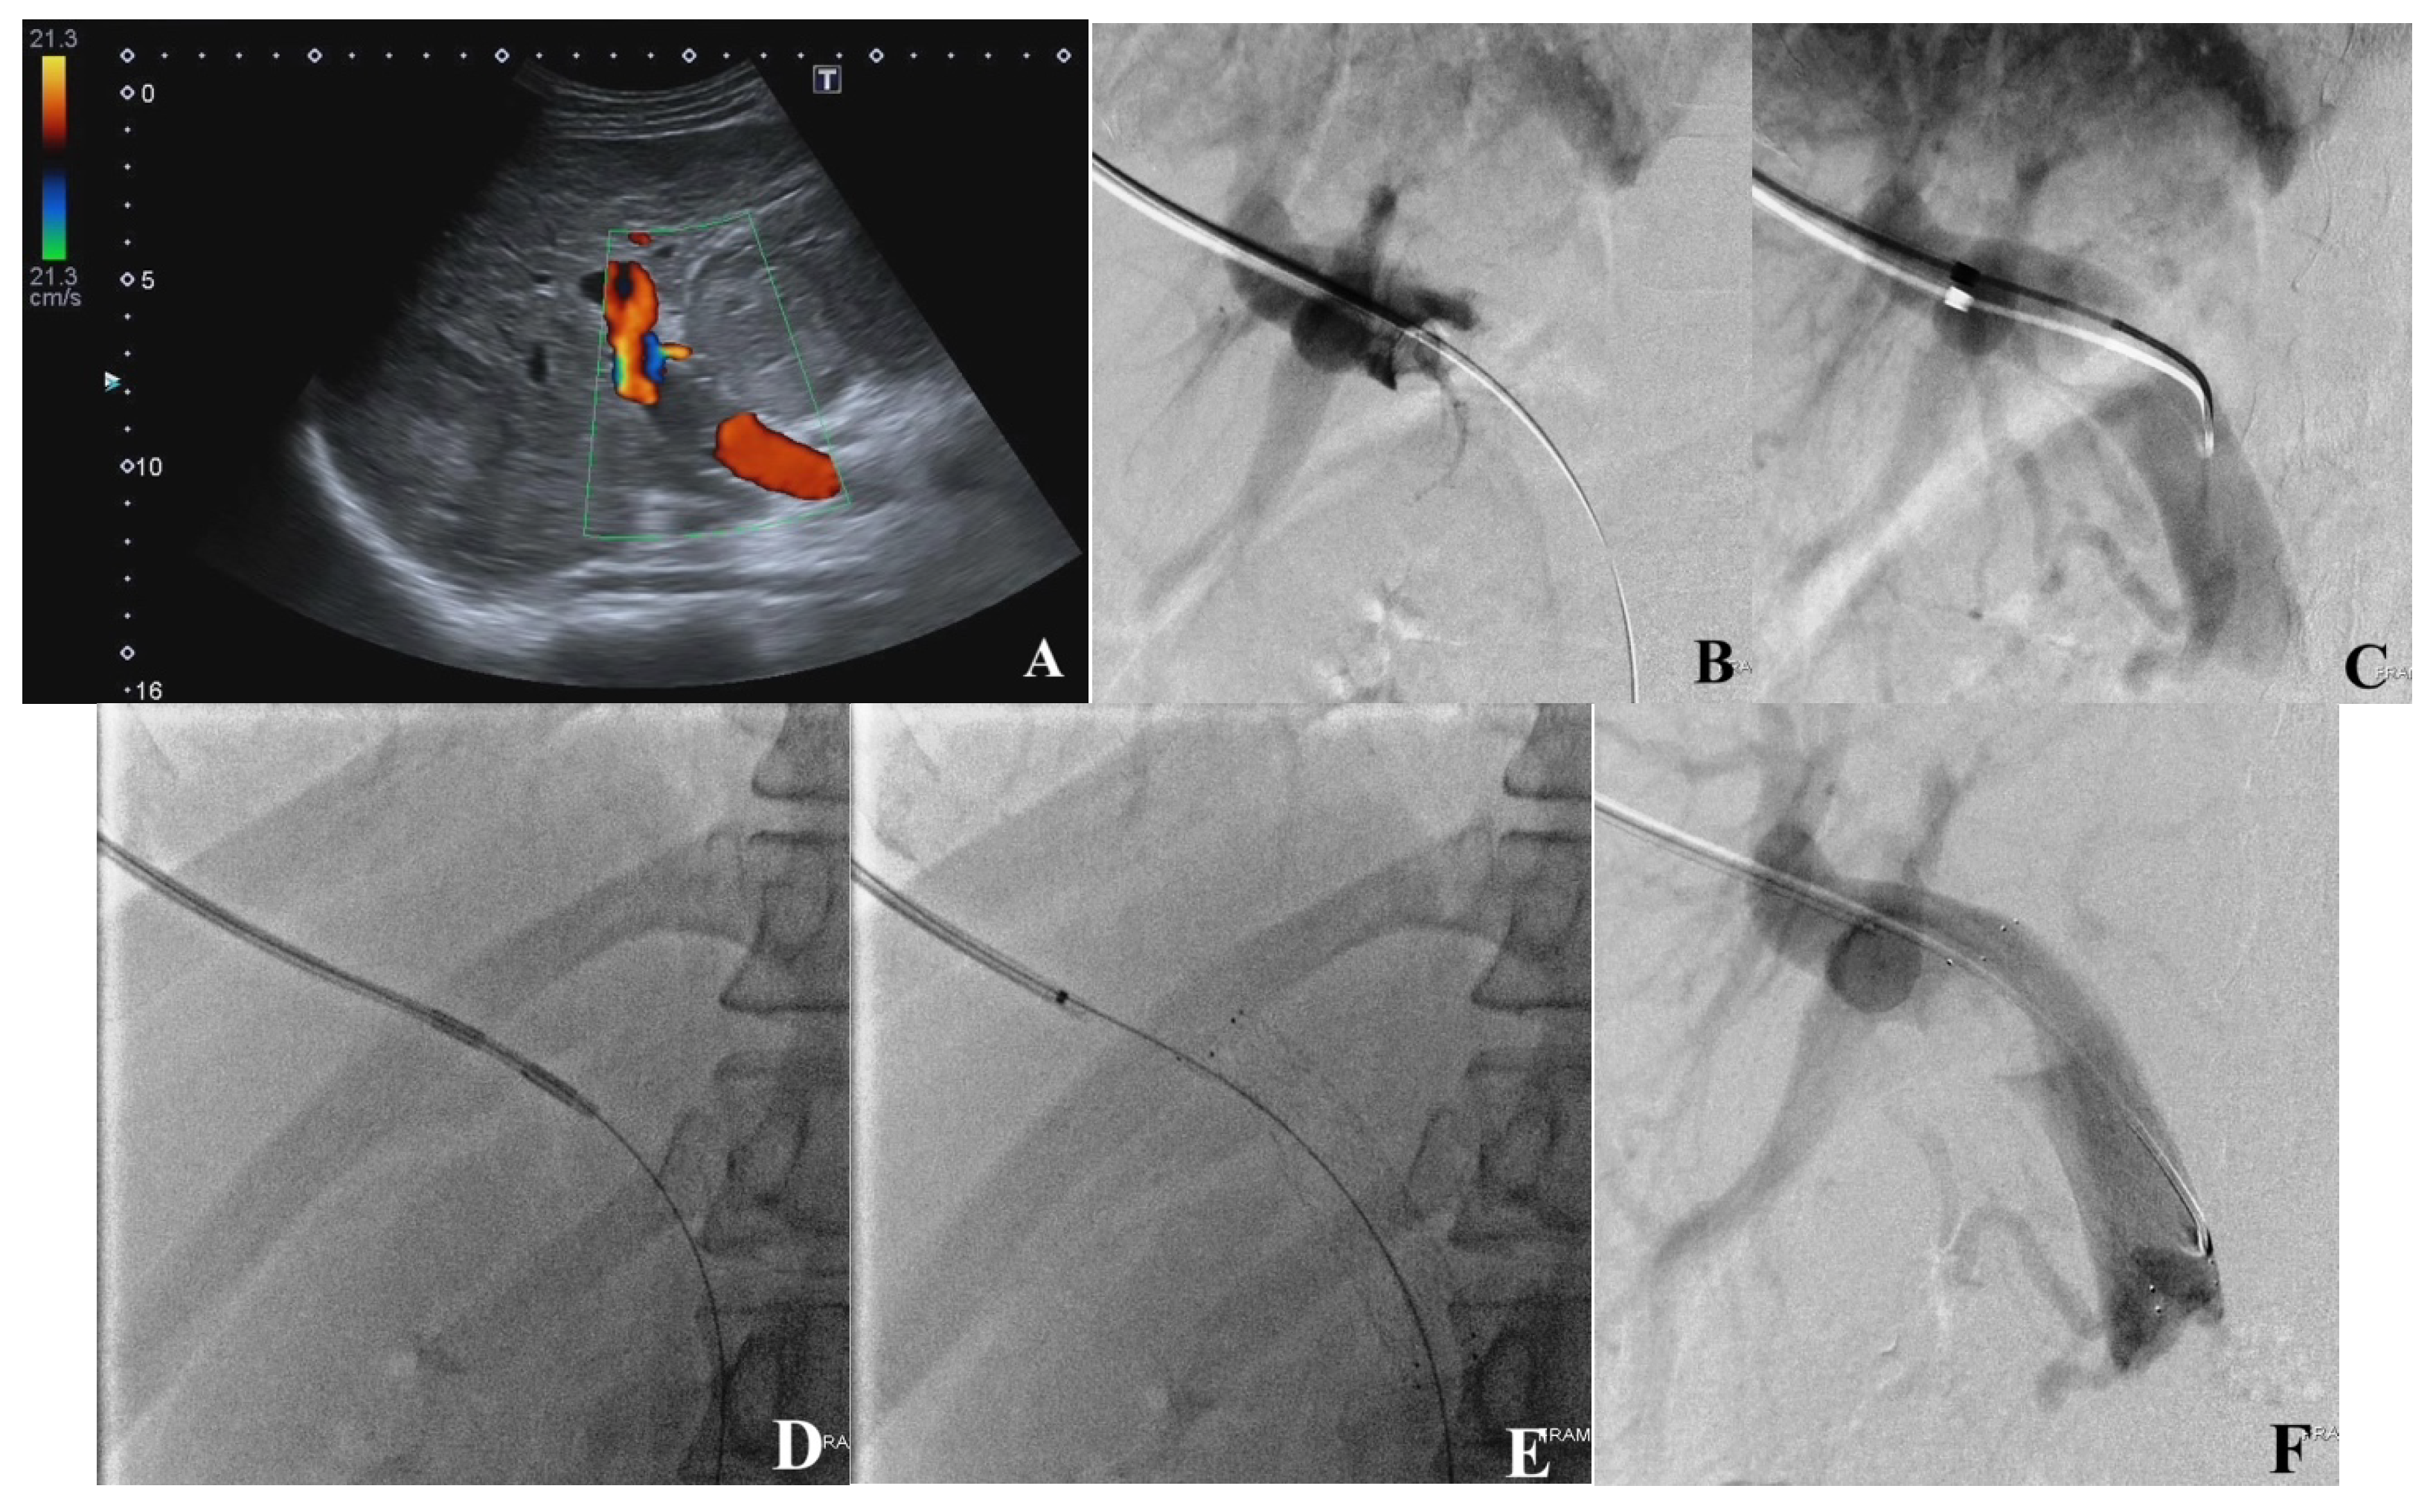

2.4. Portal Vein Access, Venogram, and Recanalization (PVR)

2.5. Endoportal Radiofrequency Ablation

2.6. Portal Vein Stent Placement